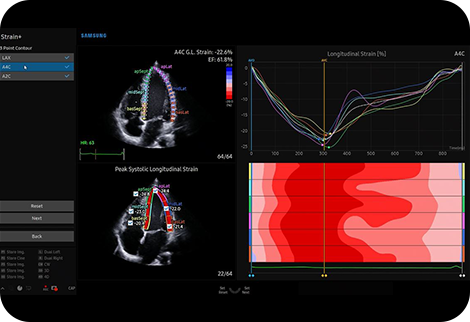

Kvantifikace pohybu stěny levé komory |

Strain+ je kvantitativní nástroj pro měření globálního a lokálního pohybu stěny levé komory (LK). V funkci Strain+ jsou zobrazeny tři standardní pohledy na LK a souhrn ve vzoru terče na jedné obrazovce pro snadné a rychlé posouzení funkce LK.

![]()